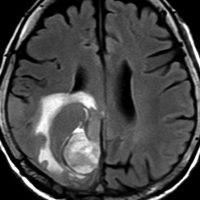

40代女性の後頭部傍矢状洞部の硬膜に発生したグレード3です。腫瘍周囲の強い浮腫のために,頭頂葉のゲルストマン症候で発症しました。術前診断は髄膜腫でしたが,腫瘍内部にのう胞(液体が溜まっている)があり,髄膜腫としては典型的な画像ではありません。右側の血管撮影にみられるように,上矢状洞が一部狭窄して腫瘍が浸潤している所見があり,腫瘍が濃染します。腫瘍の周囲の脳には出血がありました。大脳鎌と上矢状洞の壁を含めて全摘出しました。

画像と病理所見4

40代男性の大脳鎌テント接合部の硬膜に発生したグレード3です。激しい出血のために腫瘍摘出を部分摘出で中断せざるを得なかった例です。

この例でも,硬膜発生腫瘍ということは手術前の画像診断で解ってはいたのですが,髄膜腫と異なり不整な形をしてのう胞があり,一部は腫瘍壊死でした。

上の2例は,髄膜腫とは違うと一見してわかる,典型的なSFT/ヘマンジオペリサイトーマの例ですが,髄膜腫と鑑別できないようなものの方が多いです。